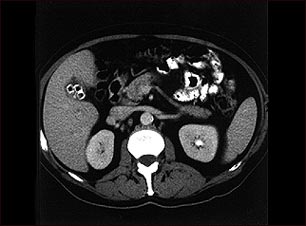

Colecistolitiasis. TC del abdomen superior mostrando múltiples cálculos biliares.